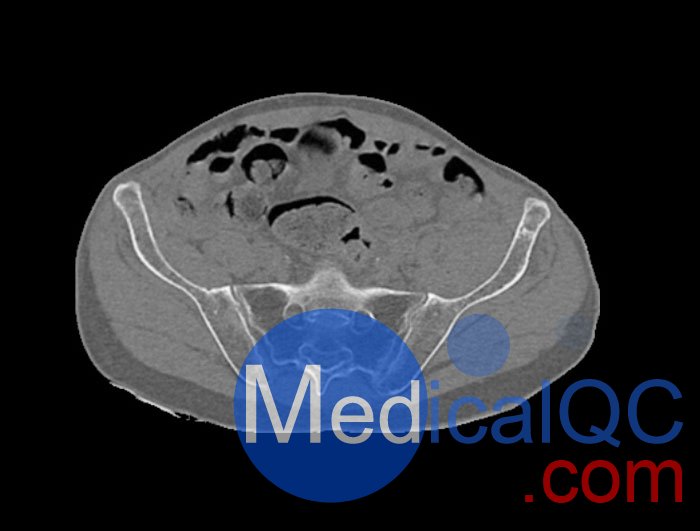

WEK54-01股骨頸骨折骨盆模型,WEK54-01骨盆模體模擬沒有靜脈造影劑的骨盆(天然)。它覆蓋了整個骨盆,直到第五腰椎。

左側股骨頸移位骨折。

該模型可用于 CT(包括 CBCT)和射線照相,以評估和優化成像性能和后處理應用,包括支持 AI 的應用。它也適用于培訓目的。

WEK54-01股骨頸骨折骨盆模型,WEK54-01骨盆模體提供了對軟組織和骨組織的詳細而逼真的模擬。空隙中填充著約-160HU的纖維素-聚合物復合材料。

骨骼和軟組織的逼真模擬。

WEK54-01股骨頸骨折骨盆模型,WEK54-01骨盆模體成像效果圖: